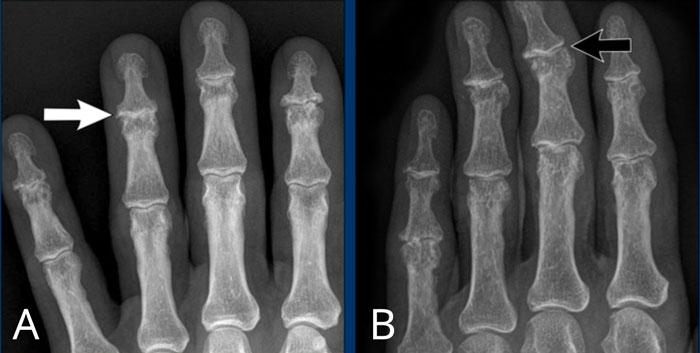

Ngón xúc xích

Hình ảnh điển hình của viêm ngón tay (dactylitis) “ngón xúc xích” với phù nề mô mềm và biến dạng bút chì trong cốc tại khớp liên đốt xa (DIP) 1-2 và 5 của bàn tay trái ở bệnh nhân viêm khớp vảy nến.

Lưu ý rằng các khớp bàn ngón tay (MCP) không bị tổn thương (khác với viêm khớp dạng thấp).

Viêm khớp vảy nến tiến triển

- Hình bên trái cho thấy bào mòn xương ở rìa khớp (mũi tên đen) và hình thành xương mờ nhạt (mũi tên xanh) tại khớp liên đốt ngón (IP).

- Về sau, bệnh tiến triển thành biến dạng bút chì trong cốc điển hình.

Phân bố tổn thương và sự hình thành xương khiến chẩn đoán viêm khớp dạng thấp ít có khả năng.

Các bào mòn xương ở rìa khớp và sự vắng mặt của tổn thương khớp liên đốt xa (DIP) ở các khớp khác khiến chẩn đoán viêm xương khớp bào mòn ít có khả năng, mặc dù biến dạng bút chì trong cốc có thể trông giống biến dạng cánh hải âu trong viêm xương khớp bào mòn.